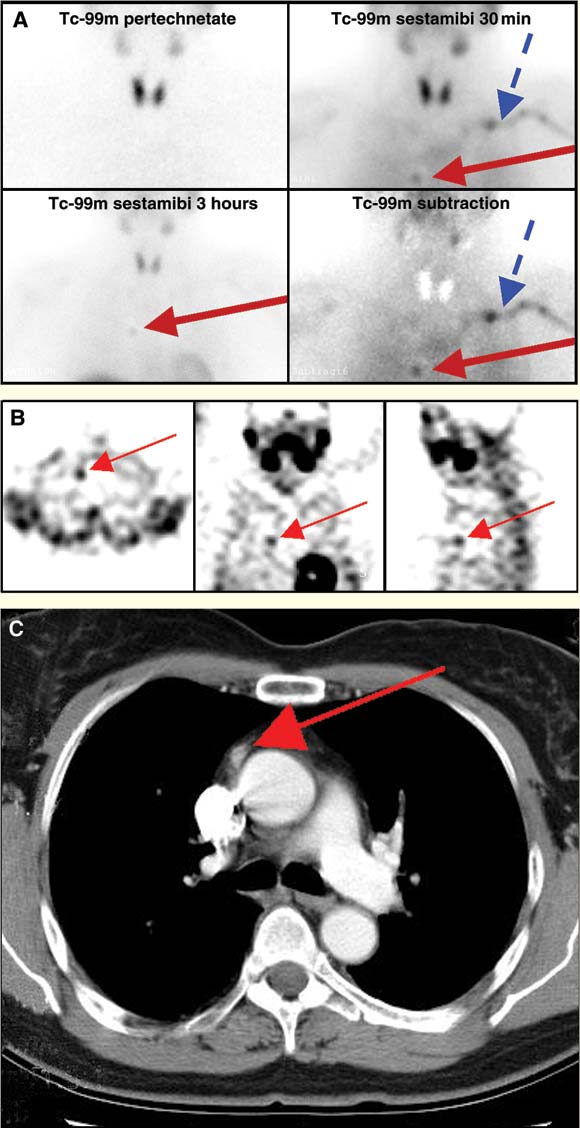

2: Preoperative imaging in a patient with raised levels of plasma corrected calcium, intact parathyroid hormone and ionised calcium

A: Tc-99m-pertechnetate-sestamibi subtraction imaging, confirming an ectopic focus of tracer activity in the chest to the right of midline (red arrow). Retained activity in the left subclavian vein is incidentally noted on the 30-minute sestamibi scan and on the subtraction image (blue arrow).

B: Transaxial, coronal and sagittal single-photon-emission computed tomography (SPECT) slices, indicating focus of increased sestamibi activity (red arrow) in the right anterior mediastinum.

C: Oval lesion (9 mm) in anterior mediastinum to the right of midline, thought initially to be non-pathological lymphoid tissue (red arrow).

A dual-phase, dual-tracer technetium (Tc)-99m-pertechnetate/Tc-99m-sestamibi nuclear medicine study revealed a solitary focus of abnormal tracer uptake in the anterior mediastinum on both initial and delayed sestamibi images and on subtracted images (Box 2, Figure A). Retained activity in the left subclavian vein was noted incidentally. No abnormality was seen within the thyroid bed. It was suspected that the activity indicated ectopic parathyroid tissue, although it may have represented retained activity within a large vessel.

Single-photon-emission computed tomography (SPECT) imaging confirmed the finding in the right mediastinum (Box 2, Figure B). Thoracic computed tomography (CT) showed a 9 mm soft-tissue mass, lying anterior to the aorta at the level of the carina (Box 2, Figure C). Its appearance was non-specific, but incidental lymphoid tissue was considered most likely. Utilising a software co-registration package (Philips/ADAC Laboratories, Milpitas, Calif, USA), the sestamibi SPECT images were fused onto the CT images. The resulting views showed abnormal mediastinal sestamibi activity localised to the soft-tissue mass, suggesting the presence of ectopic parathyroid tissue (Box 3).